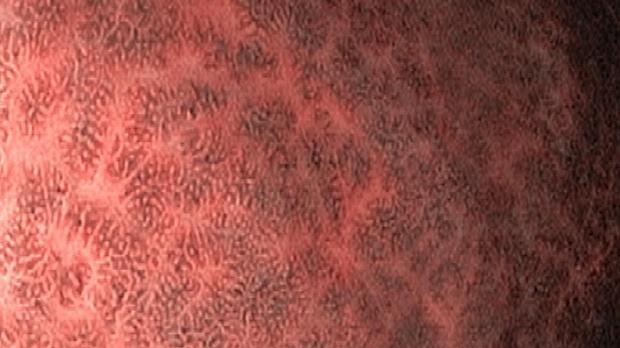

Появление ультратонких гастроскопов с высоким разрешением и технологией NBI (оптического узкоспектрального режима) компания OLYMPUS сделала возможной гастроскопию экспертного уровня под местной анестезией, без наркозных рисков.

Ультратонкие гастроскопы GIF-XP170N и GIF-XP190N с параметром оптики Close Focus, который позволяет приближаться к слизистой на минимальную глубину резкости до 2 мм, обеспечивают качество изображения, сопоставимое с аппаратами экспертного класса.

В Центре Экспертной Эндоскопии, г. Симферополь с июня 2018 с помощью этих эндоскопов выполнено более 1000 эндоскопических исследований, с полным соблюдением критериев качества ESGE. Среднее время исследования составило 14мин. 51с. Все исследования выполнялись с предварительной подготовкой желудка, применением водяной помпы и СО2-инсуффлятора, фото- и видеодокументацией.

Использование в ежедневной рутинной практике современных ультратонких эндоскопов высокого разрешения с технологией оптического узкоспектрального режима (NBI® OLYMPUS™) под местной анестезией позволило полностью обеспечить соответствие критериям качества выполнения эндоскопических исследований, определенным ESGE. Данный метод комфортен для пациента под местной анестезией, безопасен, является простой и удобной альтернативой ЭГДС под седацией, что особенно важно в амбулаторных условиях.